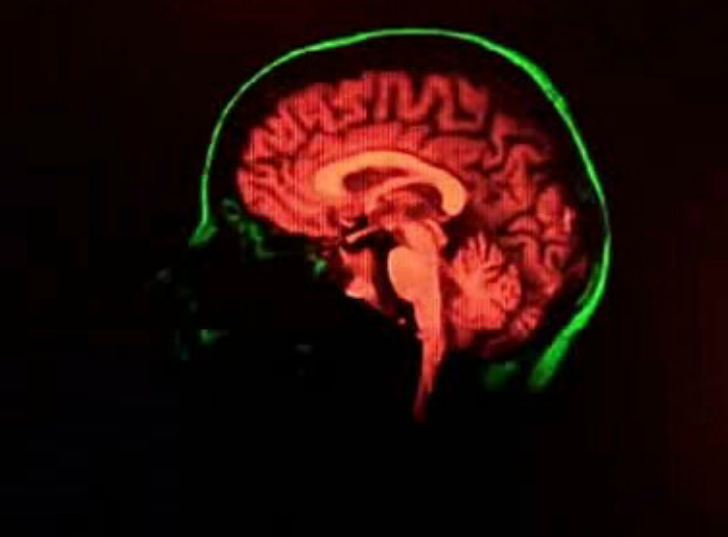

Jornalista João Tomé de Carvalho entrevista em estúdio Joana Nunes, médica gastrenterologista, sobre a doença encefalopatia hepática que afeta o funcionamento do cérebro devido a problemas no fígado, e o aumento de casos em Portugal.